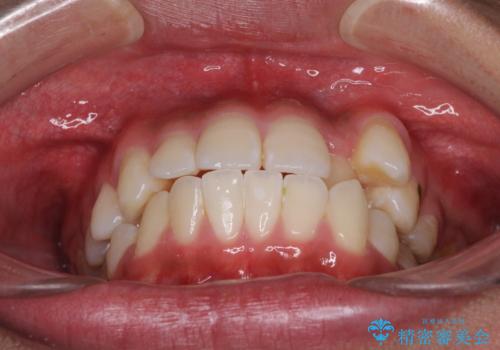

八重歯と奥歯のクロスバイト 上顎骨を拡大してインビザラインで矯正

- 八重歯を気にして来院された患者様です。

八重歯が著しいため、抜歯矯正も視野に入れて検討しましたが、臼歯の咬合関係は正常に近かったので、非抜歯矯正で進める方針としました。

上顎骨の幅が狭く、奥歯がクロスバイトとなっていたため、急速拡大装置を用いて上顎骨を側方拡大し、八重歯を収めるスペースを獲得しつつクロスバイトを改善することとしました。

上顎骨を思い通りに拡大できたため、当初の計画通りに非抜歯矯正で仕上げることができました。